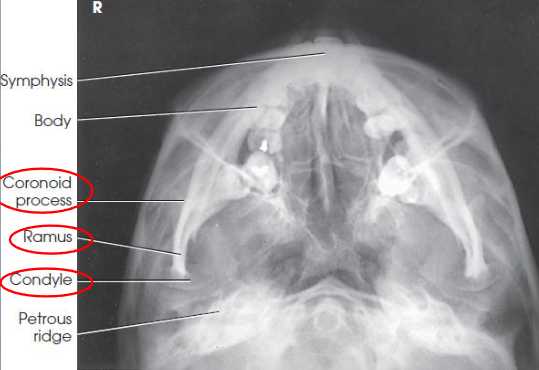

SMV mandible

patient position:

upright or supine

part position:

MSP centered to midline

neck fully extended

head resting on its vertex

MSP vertical

IOML as parallel as possible with IR

if neck cannot be flexed enough, angle the grid device and place it parallel to IOML

respiration suspended

CR:

perpendicular to IOML

centered midway between mandibular angles

if neck cannot be flexed enough, angle the tube to be parallel to IOML

collimation:

1 inch beyond the loateral sides and above the tip of the nose

SMV mandible image criteria

coronoid and condyloid processes of the rami

no rotation or tilt

equidistant lateral border of skull and mandible

MSP of head aligned to long axis of collimated field

condyles of mandible anterior to pars petrosal

symphysis extending almost to anterior border of the face

mandible not foreshortened